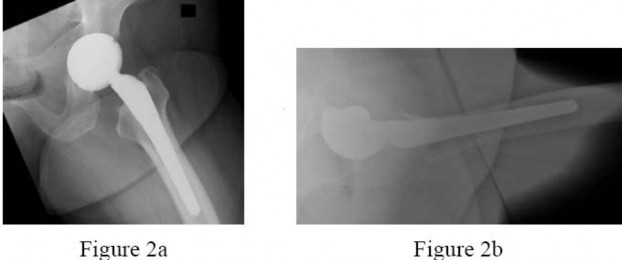

Figures 2a and 2b are the radiographs of a 56-year-old woman who has groin pain and decreased function 15 months after a total hip replacement using the posterolateral approach. Findings from the workup for infection are negative and physical examination localizes pain to the hip joint. Records show the patient underwent total hip surgery with a metal-on-metal bearing.

The patient undergoes cup revision to a more optimal position using a 36-mm metal-polyethylene bearing. Abductor muscle damage from gross metal debris and inflammation are encountered during surgery. After cup revision, repair of abductors, and hip brace use for several weeks, the patient has no more pain.Several months after surgery, the patent returns with a history of multiple hip dislocations that have proven refractory to treatment including hip precautions, bracing, and exercise. Radiographs perfectly positioned components; the patient has no pain, and examination under anesthesia shows show hip instability.

The differential diagnosis of pain after a total hip arthroplasty encompasses a number of etiologies, but the question is directed to a basic and essential part of the workup (ie, definitively considering and ruling in or out the possibility of deep sepsis). Radiographs may point to other, obvious sources of pain, but the orthopaedic surgeon must not overlook the possibility that deep sepsis is the predominant cause of the symptoms. Accordingly, ESR and CRP are logical next steps in the workup in this clinical scenario. Radiographs show increased anteversion of the metal socket, and pain etiologies can include psoas irritation, hip instability, or adverse tissue reaction to metal debris generated by suboptimal implant position leading to higher bearing contact stresses and/or impingement. Once other common etiologies of hip pain have been excluded such as deep infection or lumbar pathology, the most likely cause of hip symptoms should be considered. Here the evidence points to a malpositioned acetabular component. Systemic ion dissemination may occur in this patient but will not produce hip pain. Head-neck taper corrosion can generate metallic debris, but a more likely source of local metallic debris is edge loading or impingement of the metal-metal bearing. Leg length inequality can be distressing to a patient but will usually not result in hip pain. Component malposition is the best answer. Among the spectrum of clinical presentations following failed metalmetal total hip replacements, abductor damage from localized inflammation is one finding that can lead to hip instability. A reasonable treatment option is to repair the abductors as best as possible, with augmentation of soft-tissue repair using graft tissue, a large-diameter femoral head, and a constrained polyethylene liner. This is a challenging clinical scenario because chronic hip instability with deficient abductors is difficult to control and is an indication for the use of constrained components. Revision to a larger head and increased leg lengths will not address the underlying cause of instability. Hip resection is not necessary because this is not a septic total hip.